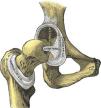

The coxofemoral joint is a ball-and-socket or spheroidal joint in which the femoral head is largely contained in the acetabulum of the pelvis (Fig. 1). Embryologically, 2/5 of the acetabulum are derived from the ilium, 2/5 from the ischion and 1/5th from the pubis. While hyaline cartilage covers the femoral head, on the acetabular side the cartilage is C-shaped leaving in the center the acetabular fossa. The C is completed into an O by the transverse ligament of acetabulum. Peripherally, the acetabular cartilague is extended by the labrum acetabulare, a tough fibrous and fibrocartilaginous rim.1,2 The ligament of the head of femur or ligamentum teres extends from the transverse ligament of the acetabulum to a fovea in the head of femur. This ligament conveys important nutrient vessels for the humeral head. The capsule of the coxofemoral joint is thickest in its upper portion where in the erect posture the load is maximal. The longitudinally-arranged external fibers of the capsule are reinforced at specific sites by ligaments that provide stability and limit certain motions of the coxofemoral joint (Figs. 2 and 3). The iliofemoral ligament or Y ligament of Bigelow, the most powerful ligament in the human body, reinforces the superior and anterior aspects of the capsule and limits extension. The pubofemoral ligament reinforces the inferior aspect of the capsule and limits external rotation in extension. The ischiofemoral ligament reinforces the posterior aspect of the capsule and limits internal rotation and adduction. Finally, the inner portion of the capsule encircles the femoral neck as a buttonhole and reinforces the joint at the orbicular zone or anular ligament. In cadaveric studies the hip position in which a given volume of effusion is at its lowest pressure is from 30 to 65 degrees of flexion, 15 degrees of abduction and 15 degrees of external rotation.3 This is the position that patients with acute arthritis of the hip spontaneously adopt. A most important point in the examination of patients with lower extremity pain is that pain that originates in the hip tends to radiate distally toward the knee. Patients are frequently surprised when they are told that an anteromedial pain in the thigh that they had previously blamed on the knee in fact originates in the hip. Hip pain typically involves the groin and the anteromedial thigh. Additional areas of radiation include the trochanteric region and the buttock. Reproduction of this pain with hip motion and an absence of pain with lumbar and knee motion should clearly incriminate the hip as the affected joint.4,5 This paper is unorthodox in that other than coxofemoral conditions and even other than regional rheumatologic conditions will be discussed. Instead, emphasis will be made on neural and vascular structures that surround the hip. This paper further emphasizes our tenet that rheumatologists are internists not only with a specialization in musculoskeletal conditions, but in the peripheral nervous system and the vascular system as well. A review of hip examination can be found in recent accounts.6–10

The hip joint with the capsule removed. Notice the ligamentum teres that connects the transverse ligament of the acetabulum and the fovea in the humeral head. The acetabulum is placed at the intersection of the iliac, pubic and ischial bones.